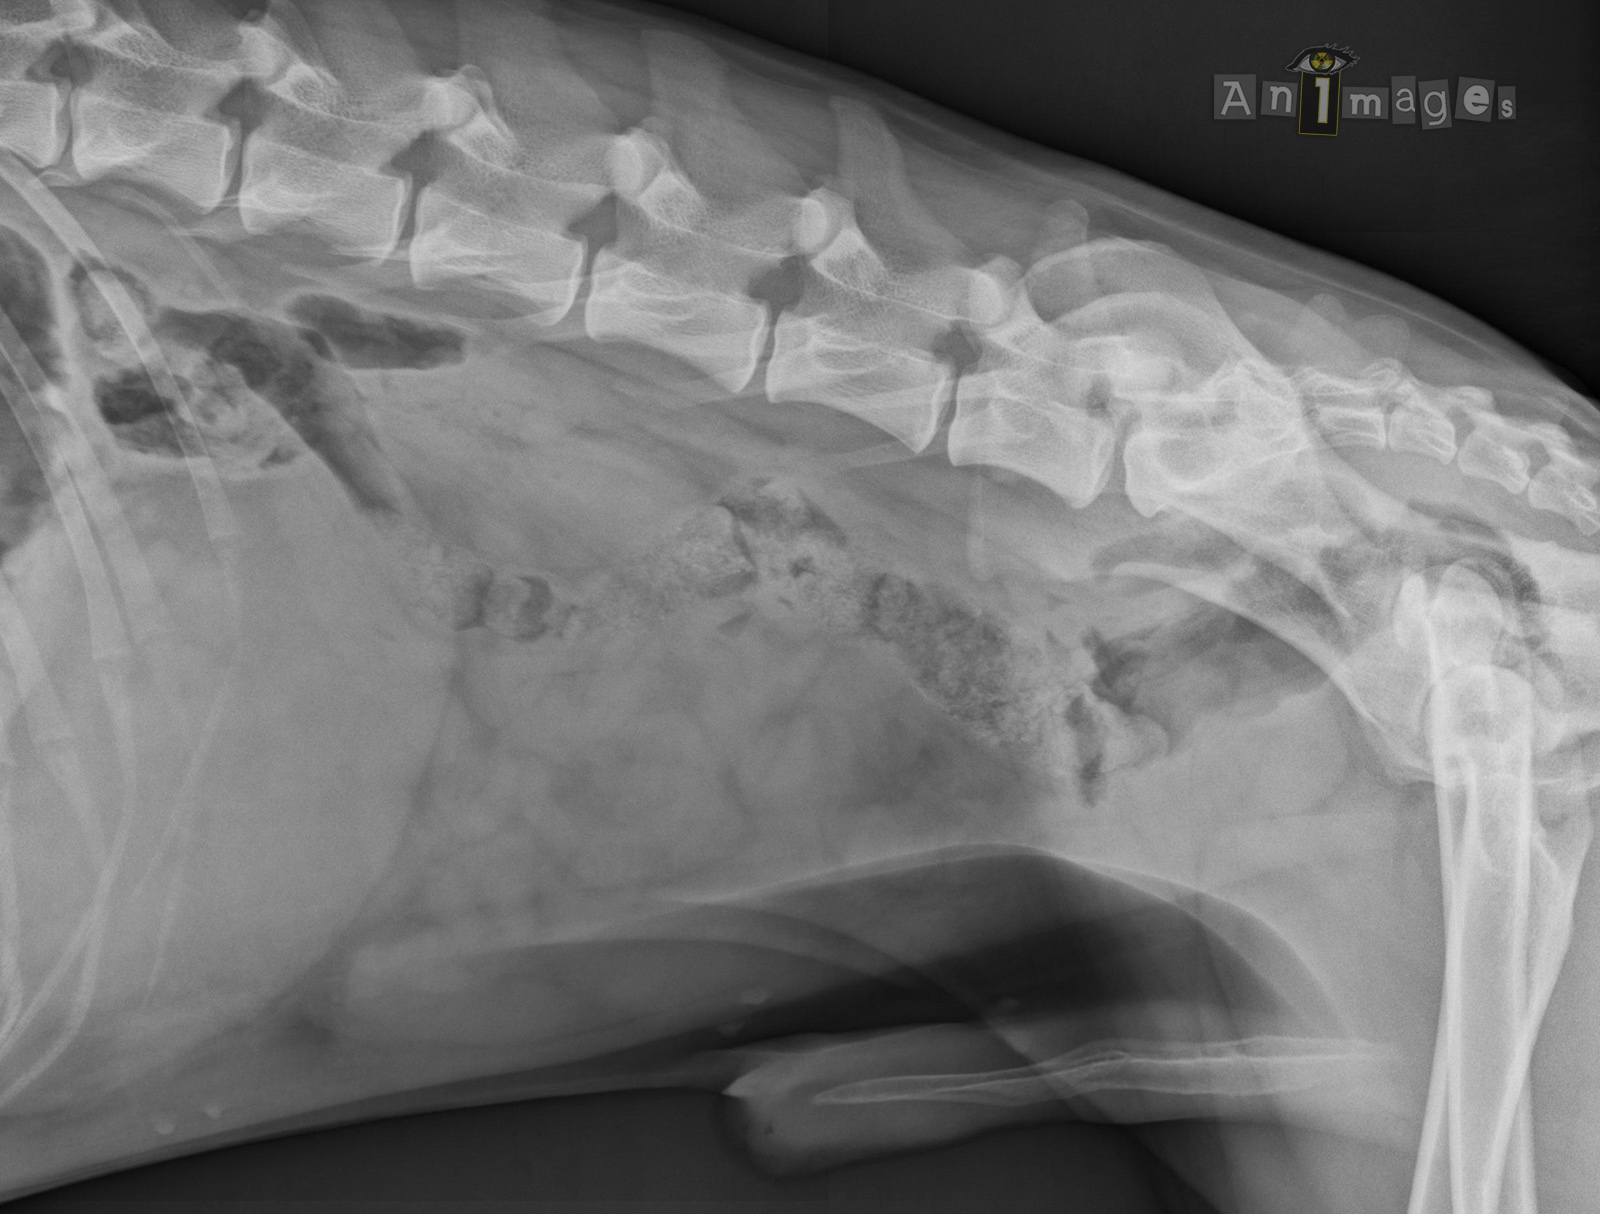

142805_RX_0002_Animages

Latérale droite 2